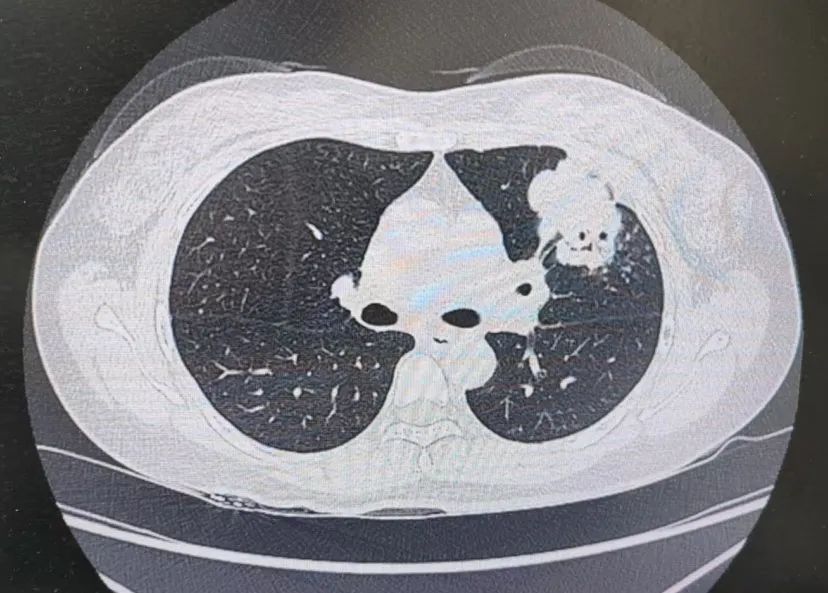

患者肺部CT影像

“一般来说,肺炎经过一周的抗感染治疗,病灶会有所吸收。但陈女士的肺部阴影纹丝不动,这种情况必须提高警惕。”宋刚主任团队立即启动了更深入的“三部精准诊断”程序:

3、CT引导下穿刺活检:病理诊断为左肺上叶腺癌。

肺炎型肺癌,因其影像学表现与普通肺炎极为相似,临床上误诊率极高。然而确诊仅是第一步。宋刚主任当天即召集肿瘤科、病理科、影像科等多学科专家会诊,为陈女士制定个体化治疗方案。